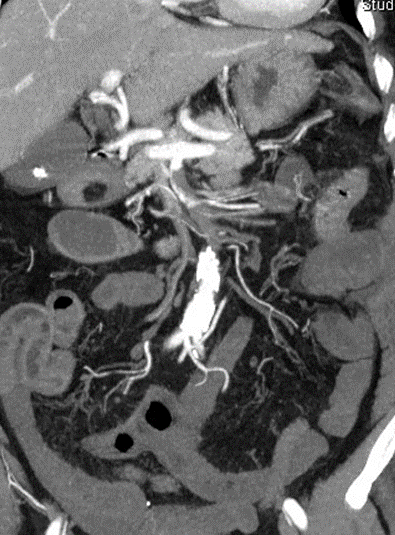

病例3:开放手术治疗

患者女性,58 岁,因 "突发腹痛 2 天" 入院,既往风心病、房颤(未规律抗凝)及颅内动脉瘤病史。查体示全腹压痛、反跳痛、肌紧张(腹膜刺激征阳性),诊断为肠系膜上动脉栓塞合并明确肠道坏死,行开腹探查 + 肠系膜动脉切开取栓 + 坏死肠道切除 + 肠道造口术,术后经营养支持及抗感染治疗,患者病情稳定出院。

图:术前影像